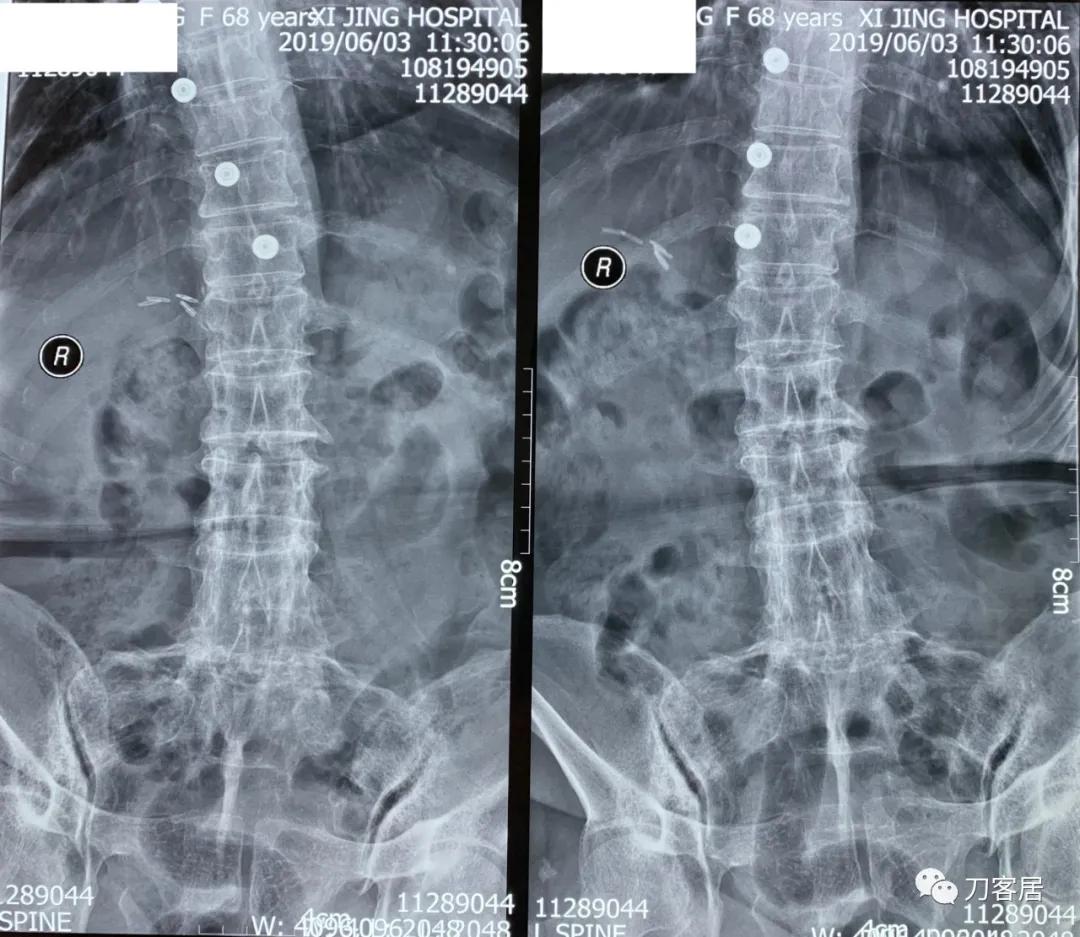

家属携带的影像学检查提示腰4-骶1病灶清除植骨融合术后改变,骨质疏松严重,未见椎旁脓肿以及结核病灶复发破坏。血沉、C反应蛋白化验检查结果正常。

诊断:腰4-骶1病灶清除植骨融合术后,严重骨质疏松症。

图2. 20190603西京医院腰椎左右侧屈正位X线片

图3. 20190603西京医院腰椎双斜位X线片